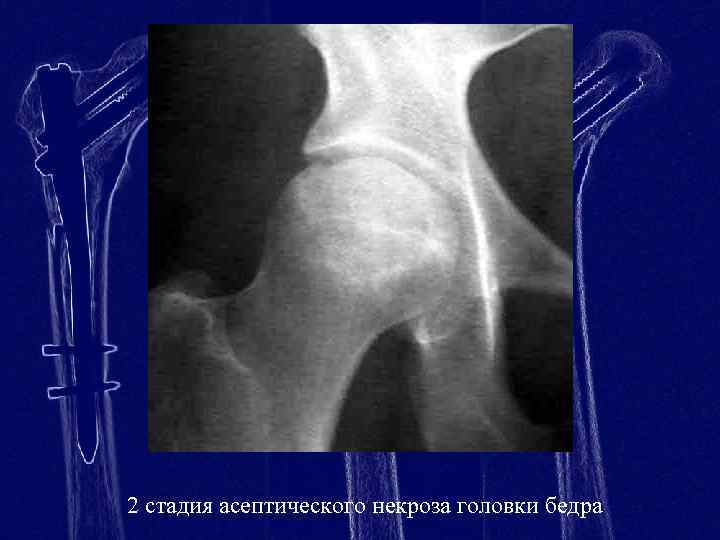

Диагностика ТБС рентгеном и асептический некроз: особенности лечения

Раздел: Снимки-откровения